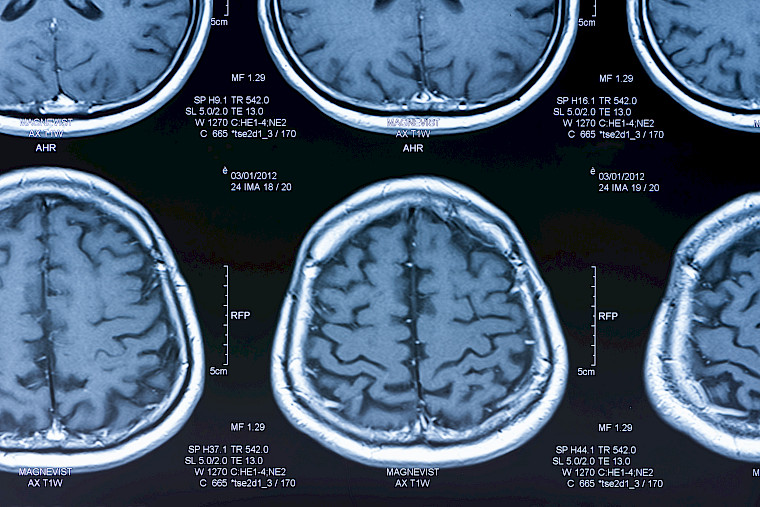

Neuroradiology is a specialised field of medical imaging. It enables highly precise examination of the brain, spinal cord and their blood supply for the detection of neurological diseases.

Neuroradiology uses various technologies such as MRI and CT for safe, gentle and accurate diagnosis of vascular diseases of the nervous system, trauma, tumours, neurodegenerative diseases, inflammatory and demyelinating diseases, and diseases of the spine and peripheral nerves.

b) Magnetic resonance imaging (brain MRI)

MRI uses a magnetic field and radio waves to obtain high-resolution images of the brain and spinal cord. This is a longer examination (20 to 45 minutes) that includes different imaging sequences. In most cases, a gadolinium-based contrast agent is injected to improve the visualization of lesions.